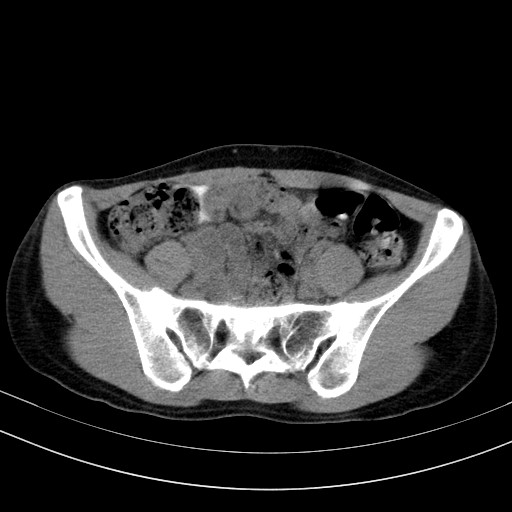

以下是引用随光逐影在2009-4-7 8:17:00的发言:[br]考虑宫颈占位性病变(宫颈癌?);建议行进一步检查。

以下是引用jiangjing在2009-4-7 16:46:00的发言:[br]宫颈增大,结构不清,右侧附件区可疑囊样占位,建议增强及mri 检查